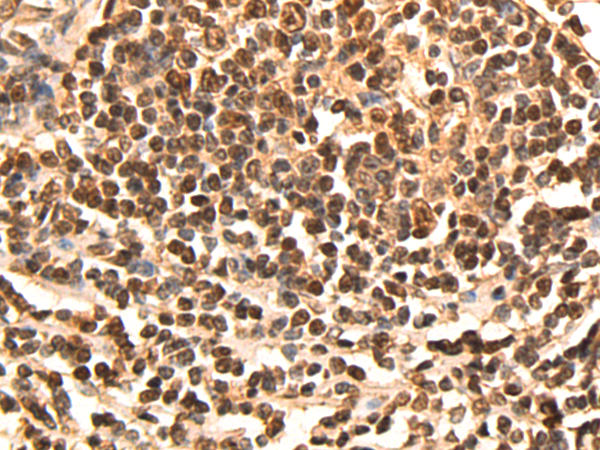

分类: 科研抗体货号: P09467别名: SORORIN应用: IHC反应种属: Human